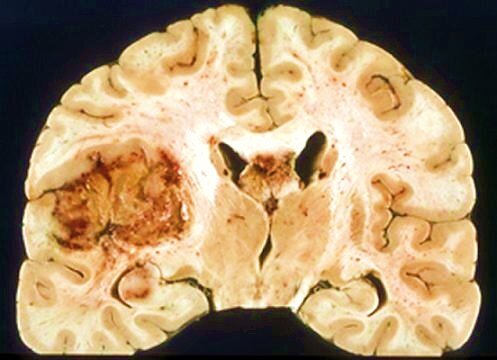

Beyin dokusunda kanserli hücrelerin (malign hücrelerin) ortaya çıktığı nadir bir hastalıktır. Kanser hücreleri, kas kontrolü, duyular ve hafıza gibi beyin fonksiyonlarına müdahale eden kanserli doku (tümör) oluşturmak için büyür. Tümörler kötü huylu (kötü huylu) ve iyi huylu (benign) tümörler olarak ikiye ayrılır. Beyin dokusundan gelişen kanser hücrelerine birincil beyin tümörleri, beyne vücudun diğer bölgelerinden yayılan tümörlere ise metastatik veya ikincil beyin tümörleri denir. İstatistikler, beyin kanserinin nadir görülen bir hastalık olduğunu göstermektedir (yılda yeni kanser hastalarının %1,4’ü). Beyin tümörlerinin sadece %5’inin nörofibromatozis ve tuberoskleroz gibi genetik nedenlere bağlı olduğuna inanılmaktadır.

Aynı beyin dokusundan kaynaklansalar bile tüm beyin tümörleri aynı değildir. Tümörler, kanser hücrelerinin mikroskop altında görünümlerine göre sınıflandırılır. Sınıflandırma ayrıca hücrelerin büyüme hızı hakkında bilgi sağlar:

Üçüncü derece: Anormal hücreler, normal hücrelerden çok farklı görünen malign dokuda aktif olarak büyüyor. Belirgin şekilde anormal (anamorfik) bir görünüme sahiptir.

Dördüncü derece: Malign doku en anormal ve hızla büyüyen hücreleri içerir.